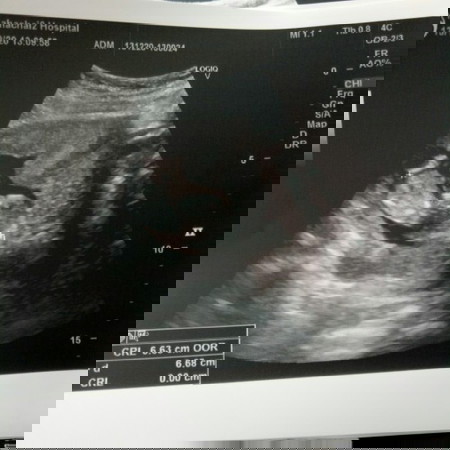

ในแอพ13วีคต้องยาว7ซม.หนัก22กรัมแล้วแต่ซาวน์มาเมื่อวานยาวแค่6.6cm17gmหมอบอกโตตามเกณฑ์ แต่ก็แอบกังวล

#ขอคำแนะนำหน่อยค่ะ สำหรับแม่13วีค